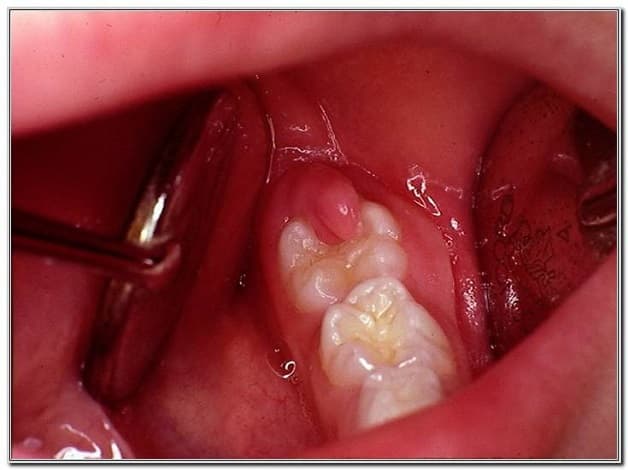

– Nhiễm trùng: thường xảy ra nếu quá trình nhổ không đảm bảo vệ sinh, quy định vô trùng hoặc vệ sinh không đảm bảo. Do vậy, khi nhổ răng khôn cần phải được thực hiện ở phòng khám uy tín lâu năm.

Nhiễm trùng hay xảy ra nếu quá trình nhổ răng không đảm bảo vệ sinh